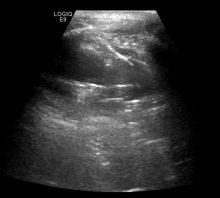

目的比较CT与超声引导下经皮肺或胸膜病变穿刺活检的有效性和安全性。方法回顾性分析2017年2月至2020年10月在湖北医药学院附属十堰市人民医院接受CT或超声引导下经皮穿刺的病灶靠近胸膜的193例肺占位患者的临床资料。根据穿刺方式将患者分为CT引导组(n=115)和超声引导组(n=78)。比较两组患者的一般临床资料、病理检查结果及穿刺成功率、并发症发生率。采用logistic回归进行单因素、多因素分析。结果CT引导组恶性肿瘤检出率(60.00%,69/115)高于超声引导组(50.00%,39/78),但差异无统计学意义(χ2=1.89,P=0.170)。CT引导组穿刺成功率(88.70%,102/115)略低于超声引导组(93.59%,73/78),差异无统计学意义(χ2=1.32,P=0.251)。CT引导组术后并发症发生率(18.26%,21/115)高于超声引导组(6.41%,5/78),差异有统计学意义(χ2=5.60,P=0.018);CT引导组气胸发生率(13.04%,15/115)高于超声引导组(3.85%,3/78),差异有统计学意义(χ2=4.65,P=0.031);CT引导组出血发生率(5.22%,6/115)高于超声引导组(2.56%,2/78),差异无统计学意义(χ2=0.82,P=0.364)。CT引导组中有1例(0.87%)患者出现严重出血需要手术治疗,5例(4.35%)需要胸腔闭式引流进行治疗,超声引导组中未出现气胸或出血需要进行引流或手术治疗患者。单因素分析发现穿刺方法为影响病变-胸膜接触弧长(LPCAL)≥38 mm的患者穿刺成功率的独立危险因素(OR=7.82,95%CI为1.57~35.50,P=0.039);多因素分析显示穿刺方法为影响LPCAL≥38 mm患者穿刺成功率的独立危险因素(OR=7.75,95%CI为1.44~41.36,P=0.042)。LPCAL≥38 mm患者中,CT和超声引导穿刺成功率分别为84.38%(54/64)、98.00%(49/50),CT引导穿刺成功率低于超声引导,差异具有统计学意义(χ2=4.52,P=0.034);LPCAL<38 mm患者中,CT和超声引导穿刺成功率分别为94.12%(48/51)、85.71%(24/28),CT引导的穿刺成功率高于超声引导,但差异无统计学意义(χ2=0.71,P=0.399)。结论超声引导下经皮肺或胸膜病变穿刺活检具有诊断正确率高、并发症少等优点,其与CT引导下穿刺活检均为胸壁病变穿刺的可行方法。当LPCAL≥38 mm时,超声引导下穿刺活检可能更具优势。

Song Tongjun, Deng Rui, Fei Lei, Lei Jinhua, Cao Fengjun. Comparison of the efficacy and safety of percutaneous needle biopsy of pulmonary or pleural lesions guided by CT and ultrasound[J]. Journal of International Oncology, 2022, 49(9): 526-531.